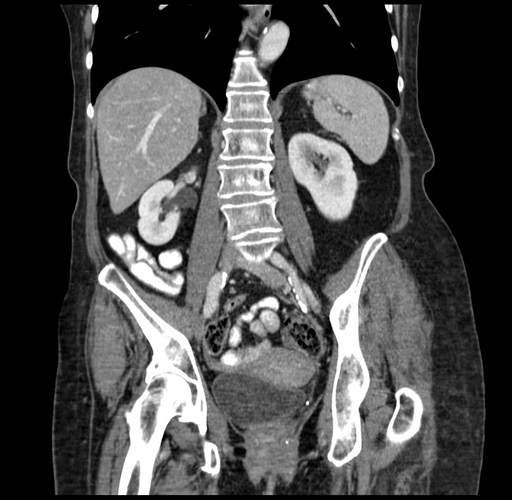

Coronal Venous